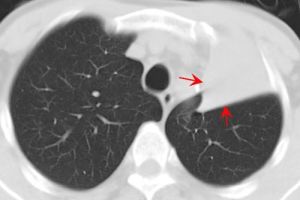

3、X線檢查X線特點為均勻緻密陰影,占據一側胸部、一葉或肺段。陰影無結構,肺紋理消失及肺葉體積縮小。一側或大片肺不張時可見肋間變窄、胸腔縮小。陰影位置隨各肺葉肺不張的部位而異。下葉肺不張在正面胸片中成三角形陰影,位於脊柱與膈肌之間,在側片中則靠近後胸壁。若繫上葉肺不張,則正面、側面影均呈楔形,其尖端向下並指向肺門。若系右側中葉的肺不張,其正面陰影呈三角形,底部位於心影的右緣,尖端指向外側;其側影為一楔形,底部近前胸壁,位於膈肌之上,尖端向後及向上。在幼嬰時期,除代償性肺氣腫之外,其他代償現象如氣管與心臟移位及膈肌上升,可暫不出現,直至肺不張持續較久後才發生。但由於表面活性物質不足造成的微型肺不張,肺多呈毛玻璃狀陰影,X線表現與小葉肺炎無異。4、病程梗阻性肺不張可以短暫或持久。肺炎、毛細支氣管炎、哮喘及支氣管炎所致粘液栓塞或黏膜水腫而形成的肺不張,時間較短,消炎去腫後即易消失。由於結核病或未取出的異物時,肺不張可較持久。雙側或大面積肺不張常迅速死亡,應立即用支氣管鏡吸出堵塞物,並進行人工呼吸搶救才可存活。

肺不張診斷主要靠胸部影像學檢查、病因,診斷需結合病史。肺不張的X線表現分直接X線徵象和間接X線徵象兩種。

肺不張的直接X線徵象

不張的肺組織透亮度降低,均勻性密度增高,恢復期或伴有支氣管擴張時可密度不均(囊狀透亮區)。不同程度的體積縮小,亞段及以下的肺不張可因有其他側枝的通氣而體積縮小不明顯。葉段性肺不張一般呈鈍三角形,寬而純的面朝向肋膈胸膜面,尖端指向肺門,有扇形、三角形、帶狀、圓形等。

肺不張的間接X線徵象

葉間裂向不張的肺側移位,如右肺橫裂葉間胸膜移位,兩側的斜裂葉間胸膜移位等;由於肺體積縮小,病變區的支氣管與血管紋理聚攏,而鄰近肺代償性膨脹,指使血管紋理稀疏,並向不張的肺葉弓形移位;肺門陰影向不張的肺葉移位;肺門陰影縮小和消失,並且與肺不張的緻密影相隔合;縱隔、心臟、氣管向患側移位,特別是全肺不張時明顯,有時健側肺疝移向患側,而出現縱隔疝;橫膈肌升高,胸廓縮小,肋間隙變窄。